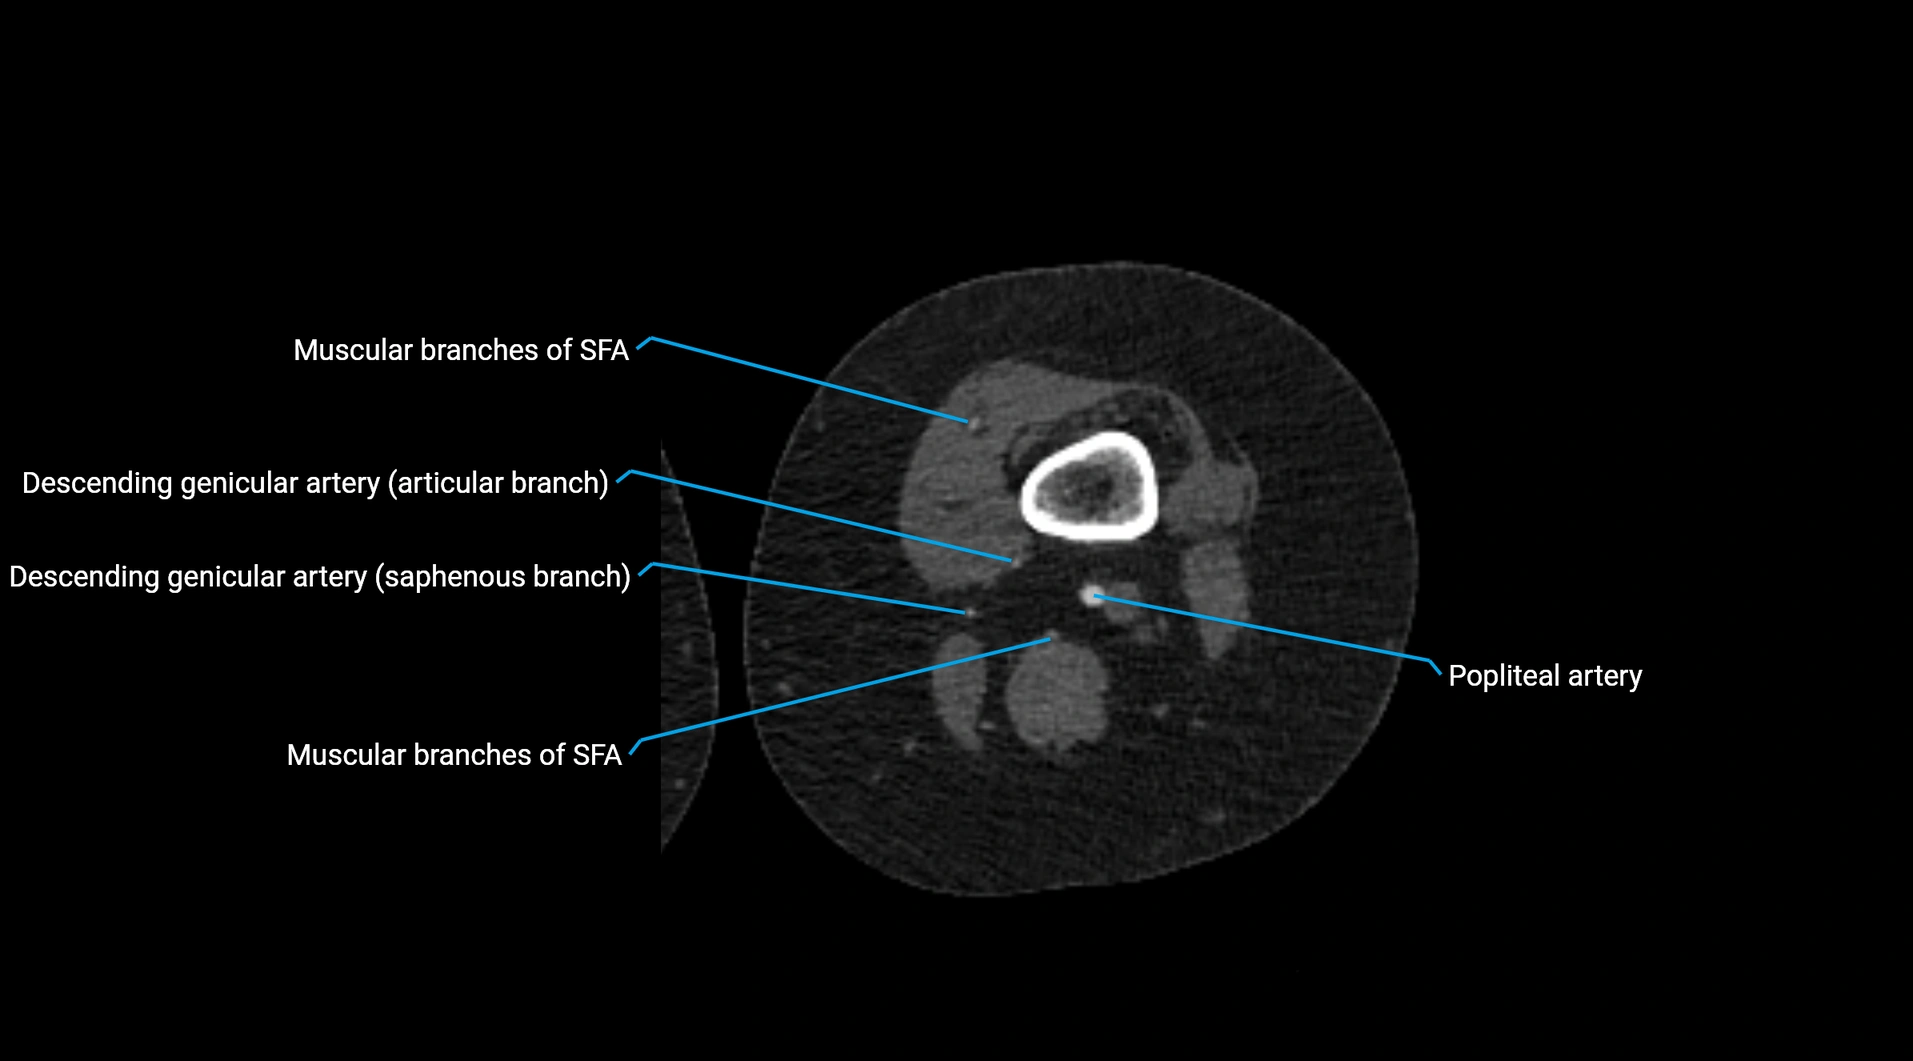

Contrast-enhanced CT (CTA):

• Gold standard for abdominal aortic imaging

• Provides excellent detail of lumen, wall, aneurysm, thrombus, and branch vessels

• Multiplanar and 3D reconstructions help in aneurysm measurement, stent graft planning, and dissection evaluation